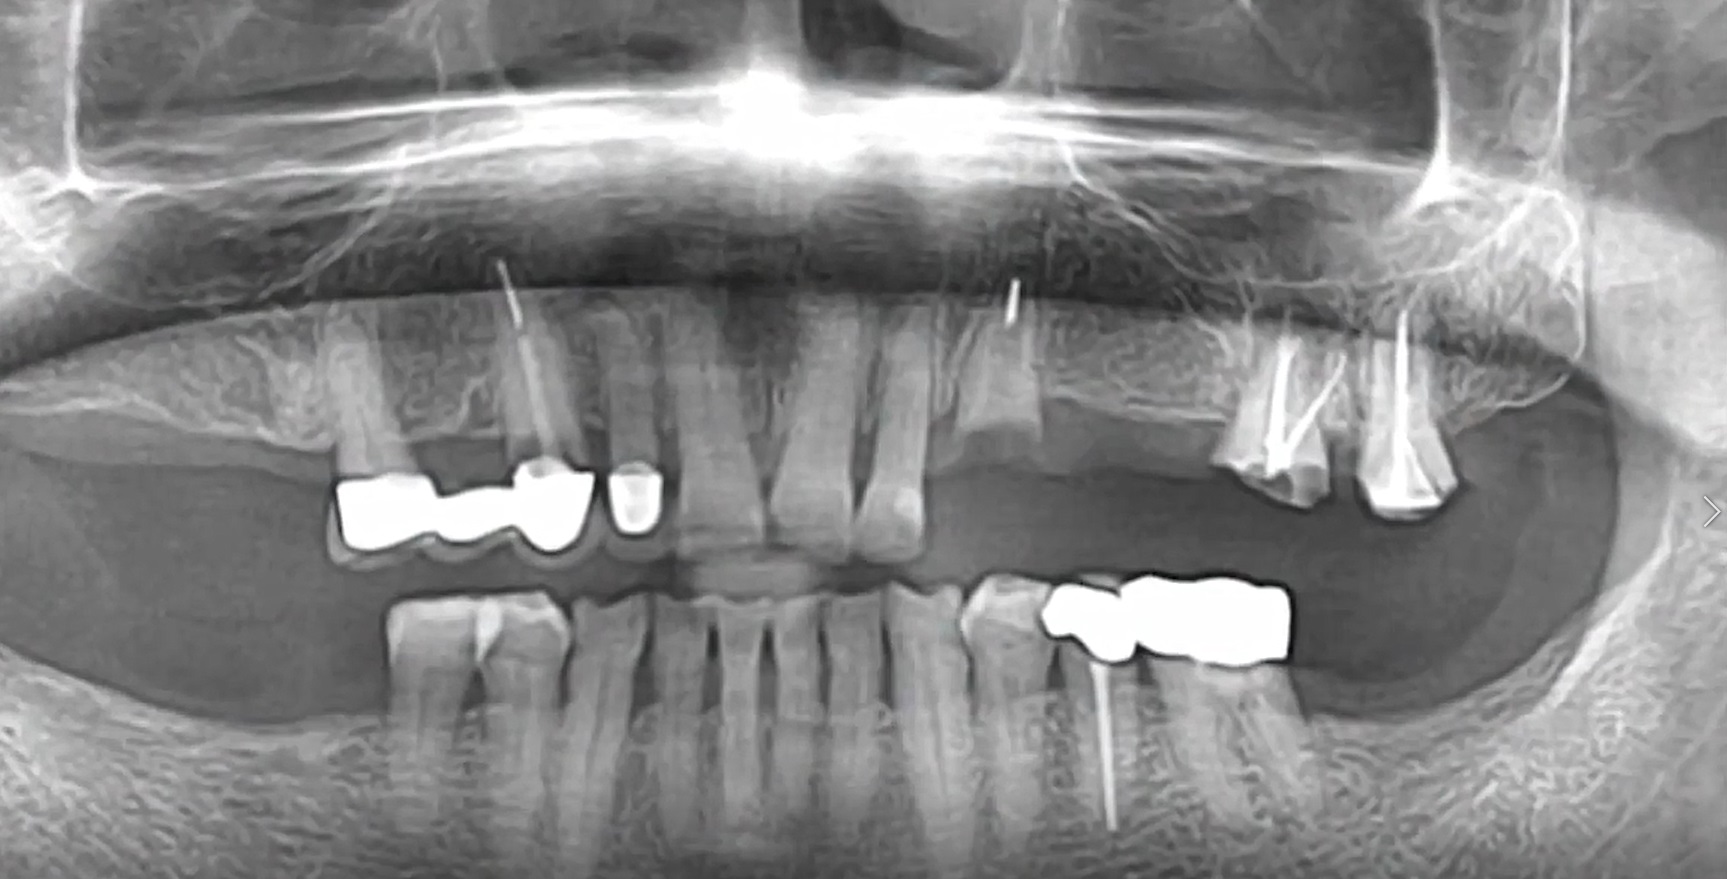

How to get a reliable ISQ!

#23,#24,#25,#26,#27,Aesthetic zone,AnyRidge,Digital,Digital Guided Surgery,Edentulous,Flapless,Immediate loading,Immediate Placement,Maxillary Posterior,MEGA ISQ,R2GATE,R2GATE Guide,R2GATE Surgical Kit(AnyRidge),video